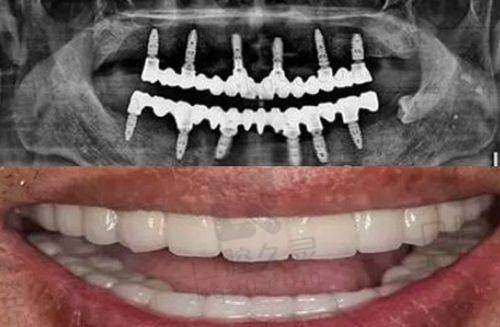

2. 种植牙技术

盐城拜博口腔医院以其专精的种植牙技术在当地享有盛誉。医院能够为患者提供个性化的种植牙方案,根据患者的口腔状况、骨质条件等因素选择合适的种植体。在无锡,一位患者选择了韩国登腾种植牙,价格是 6500 元起。医生表示这种种植牙质量好,耐用性强。经过详细检查后,医生为患者制定了个性化治疗方案,治疗后牙齿修复良好。